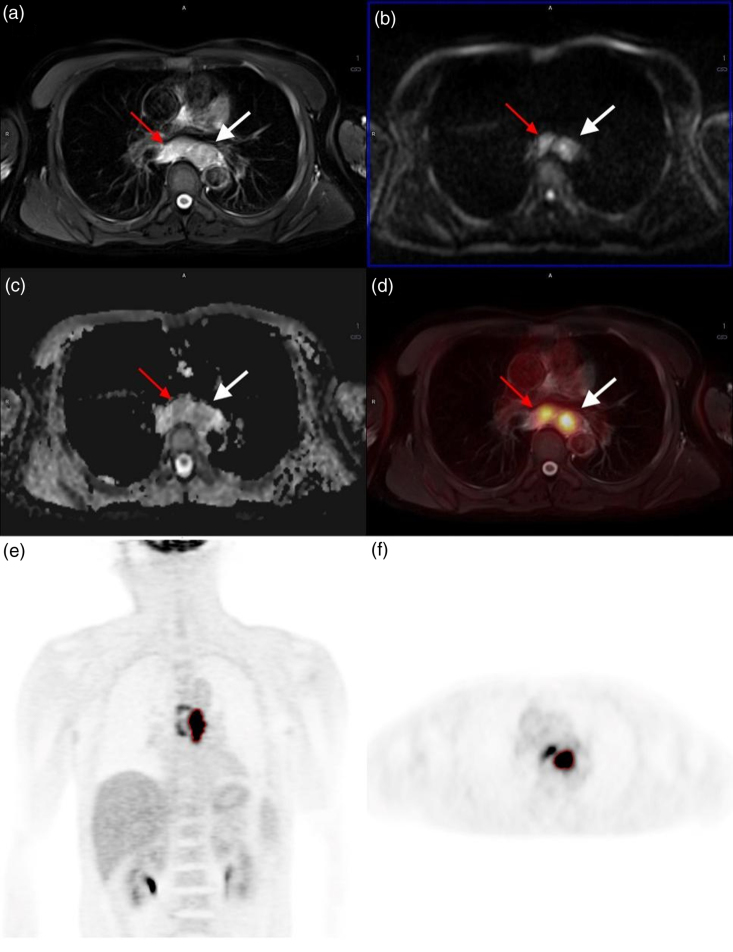

目的:探讨2-[18F]-氟-2-脱氧葡萄糖(18F- fdg) PET/MRI在食管鳞状细胞癌(ESCC)术前T、N分期及预后中的作用。材料与方法:对66例术前接受18F-FDG-PET/MRI检查的ESCC患者进行分析。我们选择原发病变作为感兴趣的区域来评估T和N分期的诊断效率。采用单变量和逐步多变量logistic回归模型确定T和N分期因素,并采用赤池信息准则建立最优预测模型。最后,采用Cox回归进行早期复发分析。结果:病灶总糖酵解(TLG)、代谢肿瘤体积(MTV)、最小表观扩散系数(ADCmin)和平均表观扩散系数(ADCmean)在T分期的单因素分析中具有显著性。在N分期的单变量分析中,所有参数均不显著。Cox回归验证了该模型结合TLG(>47.5)、MTV (>9.4 cm3)、ADCmin(结论:18F-FDG PET/MRI集成用于ESCC术前T、N分期是可行的。最优模型由TLG、MTV、ADCmin和adcmean组成,所有参数均来自18F-FDG-PET/ mri,不仅为T分期提供了有价值的信息,而且可以预测术后一年内的早期复发。

Purpose: We aimed to determine the role of integrated 2-[ 18 F]-fluoro-2-deoxy-glucose ( 18 F-FDG) PET/MRI in preoperative T and N staging and prognosis of esophageal squamous cell carcinoma (ESCC).

Materials and methods: The analysis was conducted on 66 ESCC patients who accepted 18 F-FDG-PET/MRI examinations per-operatively. We select the primary lesion as the region of interest to evaluate the diagnostic efficiency of T and N staging. Univariate and stepwise multivariate logistic regression models were performed to determine the T and N staging factors, and we established the optimal prediction model by using the Akaike information criterion. Finally, Cox regression was used for the early recurrence analyses.

Results: The total lesion glycolysis (TLG), metabolic tumor volume (MTV), minimum apparent diffusion coefficient (ADC min ), and mean apparent diffusion coefficient (ADC mean ) were significant in univariate analysis with T staging. None of the parameters were significant in the univariate analysis with N staging. Cox regression validated that this model-combining TLG (>47.5), MTV (>9.4 cm 3 ), ADC min (<1.49 × 10 -3 mm 2 /s), and ADC mean (<1.68 × 10 -3 mm 2 /s)-was the sole predictor significant associated with early tumor recurrence. Notably, no association was found between any single variable and early tumor recurrence.

Conclusion: Integrated 18 F-FDG PET/MRI is feasible for preoperative T and N staging of ESCC. The optimal model is composed of TLG, MTV, ADC min, and ADC mean -all parameters derived from 18 F-FDG-PET/MRI-which not only provide valuable information for T staging but also predict early recurrence within the first postoperative year.